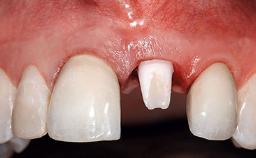

A 32-year-old female Caucasian patient with a compromised maxillary right central incisor was referred to us by a general dentist. Her chief complaints were discomfort and mobility of tooth 11 with unsatisfactory esthetics due to discoloration. The patient reported a previous trauma, some years earlier, as the origin of pathology on the afflicted tooth. Anamnesis was negative for any other dental or periodontal pathology in the remaining dentition. The patient did not take any medication and reported to be a light smoker (5–10 cigs/day). She had high esthetic expectations of her treatment. The extraoral examination revealed a high smile line with full exposure of her maxillary teeth and surrounding soft tissue in the area between the second premolars.

Provisional Implant-Supported Prosthesis Prosthodontic margin > 3 mm apical to mucosal margin Prosthodontic margin > 3 mm apical to mucosal margin

Interim Prosthesis during Healing Fixed Fixed